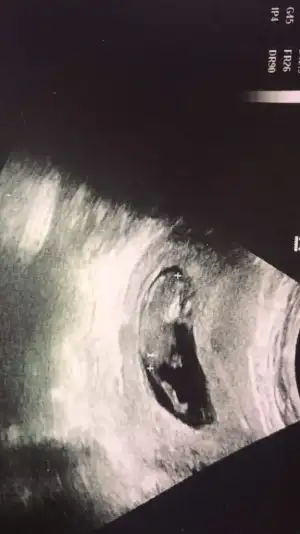

Ya arkadaşlar bebeğim 16 haftalık bugün 4 lü tarama için gittim 16 hafta boyunca bebeğe erkek diyen doktor bugun de kıza benziyo dedi şaştım kaldım nasıl öğrencem ben cinsiyeti doğru hangisi ? EKLEDİĞİM GÖRSELDE BACAK ARASINI MI ÇEKTİ BİLMİYORUM BAKAR MISINIZ.

İlk eklediğim görsel (bacaklar) dün çekildi 16 haftalık diğerleri 14 haftalıkken çekildi